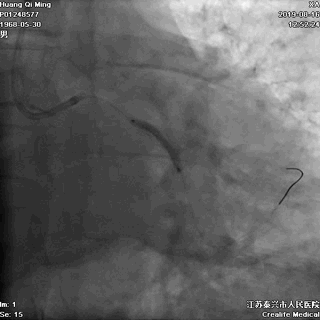

LAD PCI过程

导丝通过病变抵达血管远段

8atm,2.0*20球囊行PTCA

8atm,2.0*10 切割球囊对斑块进行切割

16atm,NC球囊对斑块进行预处理

2.0*25 药物洗脱球囊,8atm*60秒释放药物

2.5*25 药物洗脱球囊,8atm*60秒释放药物

术后即刻效果满意